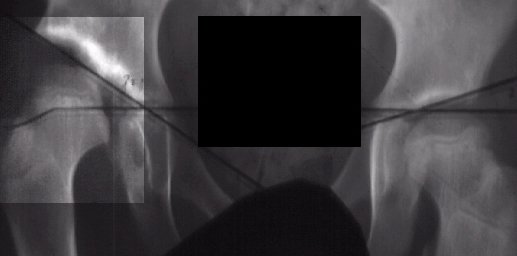

X-rays

and

arthrogram at two years of age show irregular ossification of the femoral

head and dysplastic acetabulum,

but the hip coverage was acceptable even in adduction.